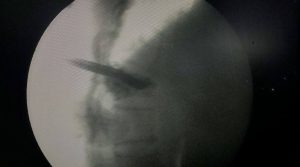

* টিউব প্রবেশ করানো: একটি পাতলা টিউব (ক্যানুলা) সেই incision এর ভিতর দিয়ে মেরুদণ্ডের ভাঙা কশেরুকায় প্রবেশ করানো হয়। এক্স-রে (ফ্লুরোস্কোপি) ব্যবহার করে টিউবটিকে সঠিক অবস্থানে নেওয়া হয়।